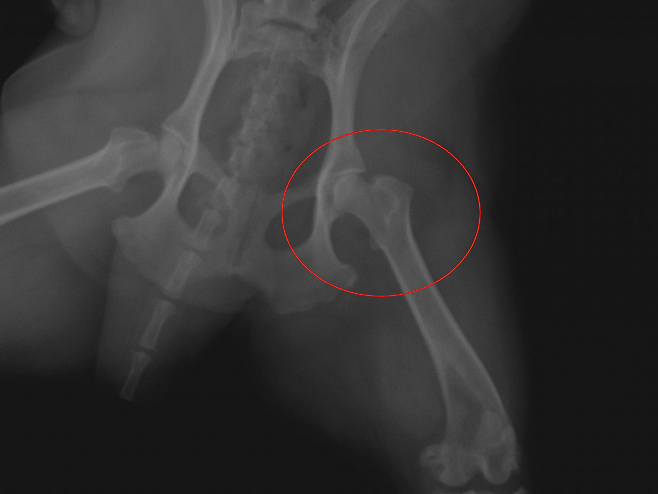

κ·Έλ κ² λͺ½μ΄μ κ΄μ κ΄λ¦¬λ₯Ό μμνκ² λμμ΄μ. μΌλ°μ μΌλ‘ μ€μν견μ κ²½μ° μ¬κ°κ³¨μ΄ μ μ’μ κ²½μ°κ° λ§λ€κ³ ν΄μ μ€νκ²¬μΈ λͺ½μ΄ μμ μ¬κ°κ³¨ νꡬλ₯Ό μμνλλ°μ. μ μ μμ€λ μ΄λ₯Ό μ°μ΄λ³΄λ νλ² μ§ λΌμ(λν΄κ³¨) 머리 λΆλΆμ΄ κ³ κ΄μ μ μ μ리μμ λ²μ΄λ κ³ κ΄μ νꡬμκ³ κ΄λ¦¬κ° νμν μνμμ΅λλ€.